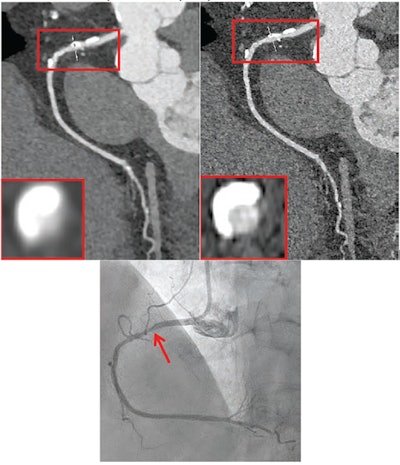

72-year-old female participant with heart failure. Patient underwent coronary CTA by photon-counting detector CTA, acquired in UHR mode. Agatston score was 1,615. Heart rate was 59 beats/min. (A) Reconstructed UHRnormal image. Proximal RCA shows calcified plaque. Inset shows cross-section of RCA at level of thin line traversing vessel. (B) Reconstructed UHRthin image. Proximal LCX shows calcified plaque. Inset shows cross-section of RCA at level of thin line traversing vessel. Insets show less blooming artifact from calcified plaque for UHRthin than for UHRnormal. Stenosis at site of calcification was measured as 60% for UHRnormal and 30% for UHRthin. (C) Image from subsequent invasive coronary angiography shows 30% stenosis of RCA (arrow). UHR = ultrahigh resolution. Images and caption courtesy of the AJR.